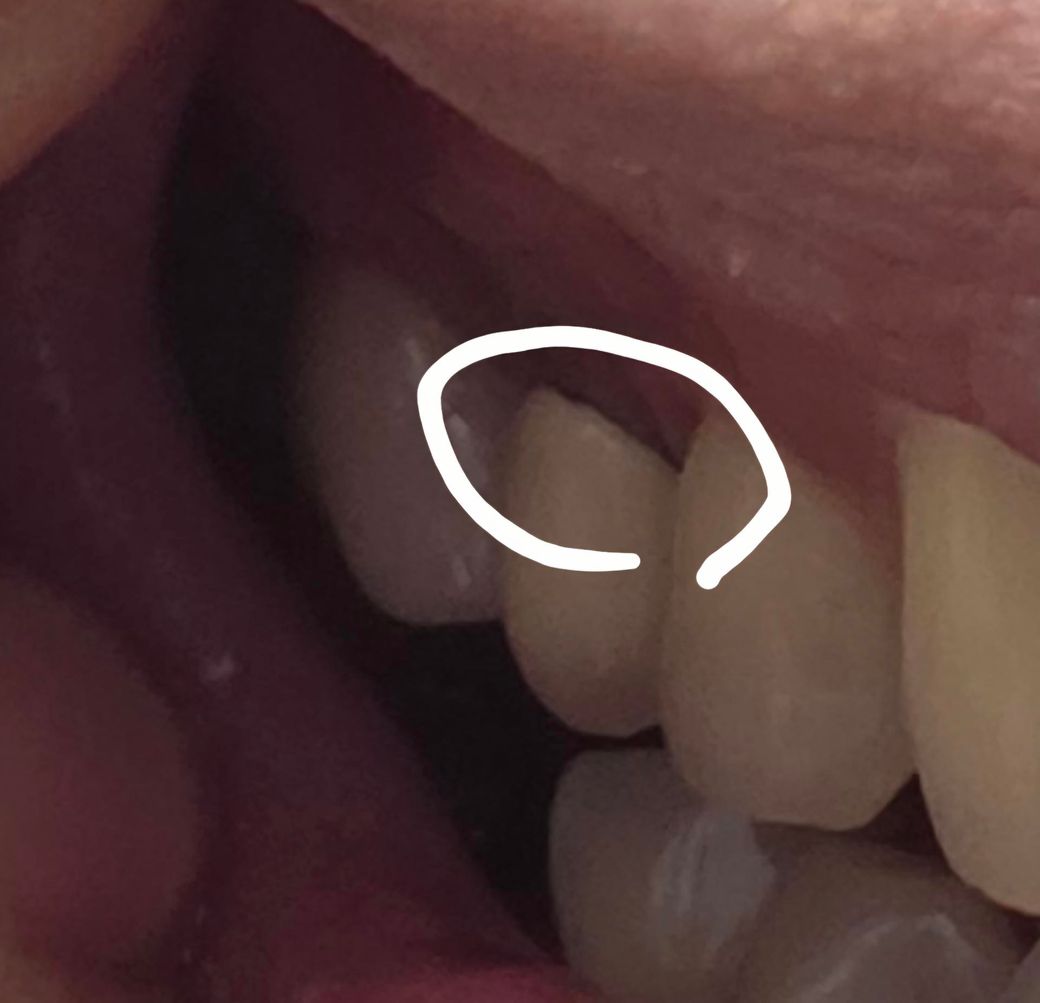

이가 썩은건가요 ?? 사진첨부합니다

동그라미 친부분이 이와 잇몸 경계선인데 저기가 까맣게 줄거져있습니다

금속이 들어가는 보철물의 경우에는 보철물의 경계부위가 어둡게 보일수 있습니다. 또한 충치가 있어도 검게 보일수 있습니다.

보통은 도자기색 pfm 보철물 하방으로 검은 선이 보이는 것이 흔한데 자연치아라고 하면 충치이거나 이물질이 낀 것 같습니다.